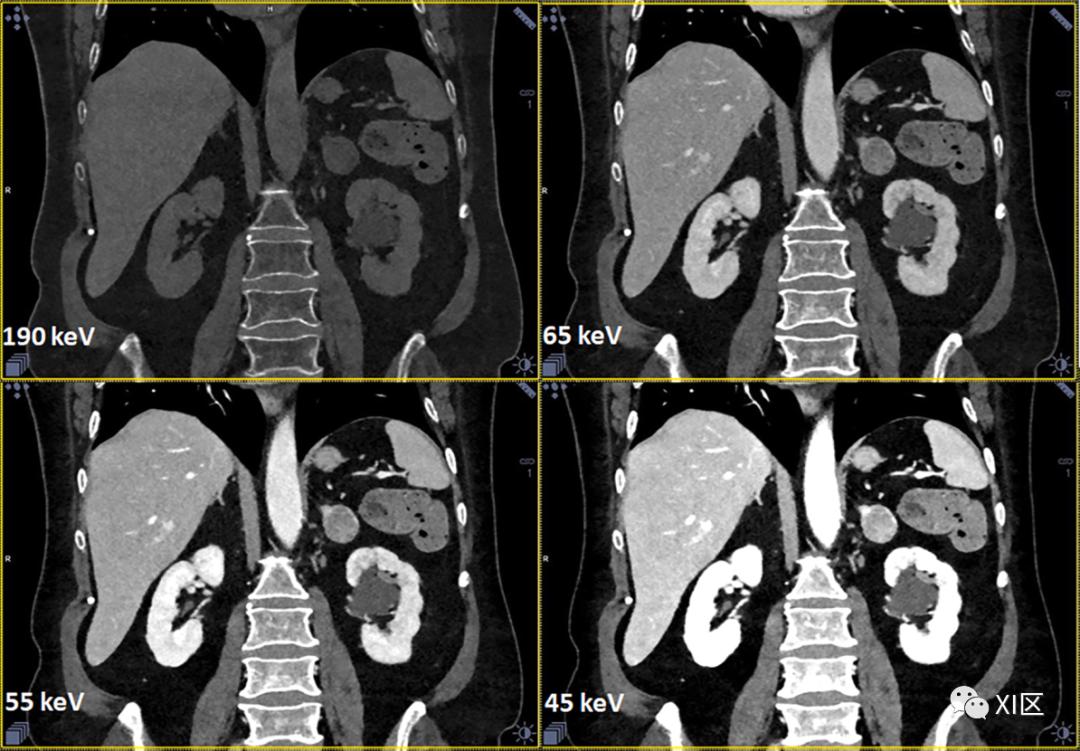

光子计数CT的VMIs的常规可用性可能为CT协议的进一步标准化铺平道路,前提是通过精细处理提高VMIs的CNR和图像质量。在这种方法中,根据临床问题定制的标准化keV水平的VMI(例如,实质器官对比增强检查为50-70keV,CT血管造影研究为40-50keV)是任何CT扫描的主要输出,而不管采集协议如何,见图14。更进一步,采集协议也可以标准化。一些作者已经推荐了一种标准化采集协议,该协议使用140kV X射线管电压,用于所有患者的腹部CT增强检查,标准化VMI重建为50keV。根据作者的说法,使用该方案可以获得所有患者大小的最佳或接近最佳的碘CNR。

图14 67岁女性患有肾上腺腺瘤和肾盂旁肾囊肿的腹部图像,采用带有光子计数探测器的临床前单源CT原型采集。数据采集:“标准”模式,144x0.4 mm准直,0.3 s旋转时间,CTDIvol=10.2 mGy,DLP=450 mGy·cm。图像重建:VMI为190 keV,65 keV,55 keV和45 keV,0.4 mm层厚。请注意,随着keV的增加,碘和钙的对比度降低-190 keV图像可以替代虚拟平扫图像。一些作者评估了光谱光子计数CT在肾结石检测和特征描述方面的性能。他们发现,在鉴别结石成分方面,整体表现与最先进的双能CT相当,而光子计数CT能够更好地帮助确定小肾结石的特征。